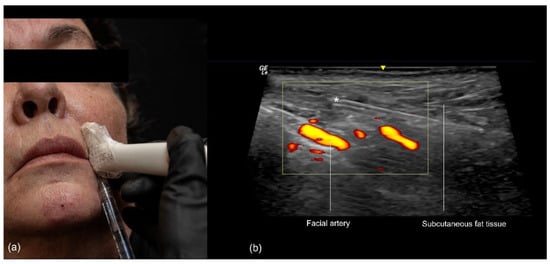

3.3. Nasolabial Fold

3.3.1. Sonographic Anatomy of the Nasolabial Fold

- Technique 1: Subcutaneous filler placement with a blunt cannula

- Technique 2: Supraperiosteal filler placement with a needle